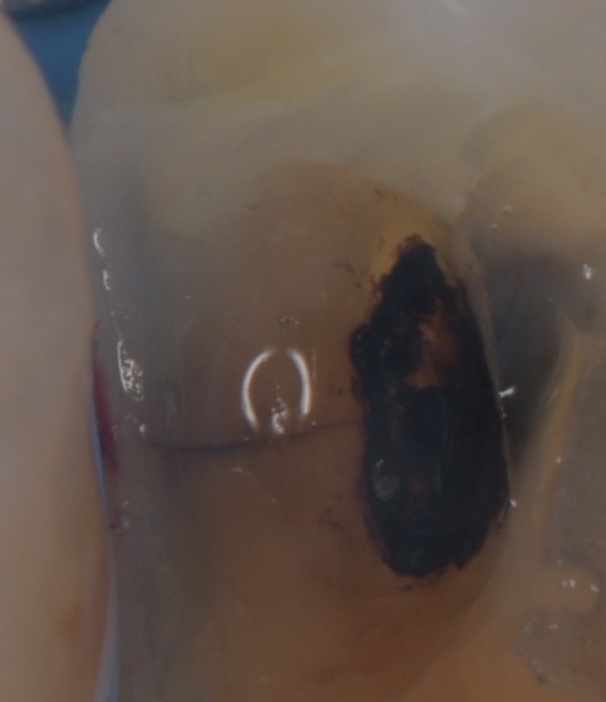

患者さんは歯がとても沁みると訴える歯医者さんでした。適切な治療を受け、セルフケアやメンテナンスを完璧にしているはずの歯医者さんでも虫歯になる事があります。 その原因は噛み合わせや生活習慣です。負荷の大きな力から歯のひび割れ(マイクロクラック)が起こり、その間を伝って細菌に栄養が運ばれ、知らないうちに進行してしまいます。 顕微鏡を使い、ひび割れを取っていきます。このひび割れが残っていると再び、細菌の感染経路となるため、可能な限りとります。これは十分な治療時間と顕微鏡がなければ不可能な仕事です。   虫歯を取っていくと神経の露出が見られました。 MTAセメントにて神経保存を行いました。 だんだんと、症状が改善してきたそうなので、今後、最終修復を行う予定です。       リスク 極端に硬いものを噛むと取れたり、かける可能性があります。 ラバーダム、顕微鏡等を使用し適正な時間を確保された治療は自由診療となります。 各種治療費はこちらから